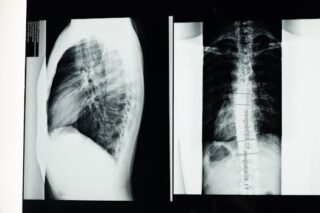

The L5-S1 vertebrae are part of the lumbar spine, which connects the spine to the pelvis. Exercises that impose excessive stress on this area can lead to discomfort or exacerbate existing issues. Let’s review some common exercises to steer clear of and explore safer alternatives.